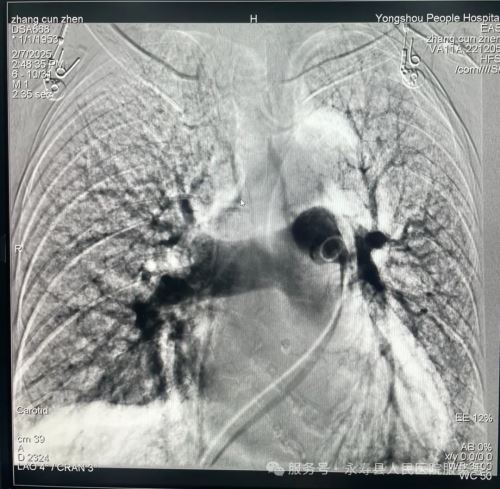

手术在上级医院专家的协助及介入科团队辅助下进行,为患者行下腔静脉滤器植入术,经股静脉植入鞘管。造影下腔静脉无血栓形成,肺动脉造影显示右上肺动脉(小动脉)中远段肺栓塞形成,肺栓塞诊断明确,是下腔静脉滤器植入绝对适应症,确定滤器的适宜型号和释放系统后,在肾静脉下端置入下腔静脉滤器,并确认其位置完好。整个手术过程历时仅30分钟,患者无不适反应,经后续治疗效果良好。

肺动脉造影